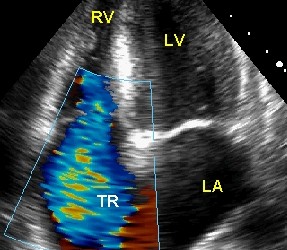

Insuficienţa tricuspidiană

Reprezint? închiderea incomplet? a orificiului tricuspidian în timpul sistolei, stuff sickness permi?ând refluarea sângelui din ventriculul drept în atriul drept.

La examenul cordului, auscultator se constată un suflu sistolic de regurgitare tricuspidiană, cu intensitatea maximă parasternal stâng, în spaţiile intercostale 4-5. Suflul este intens, uneori mai accentuat în protosistolă sau, mai rar, în mezo sau telesistolă. Poate iradia către apendicele xifoid, marginea dreaptă a sternului sau apex. Timbrul este asemănător unei „ţâşnituri de aburi”. Suflul se accentuează în inspir (manevra Rivero-Carvalho) sau în timpul manevrei Valsalva.